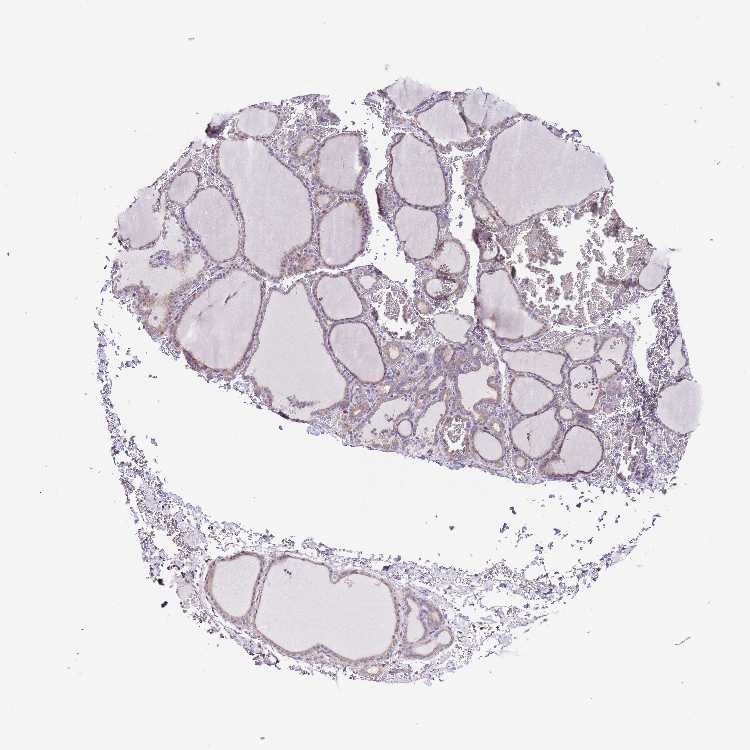

TISSUE PRIMARY DATA THYROID GLAND Show tissue menu

THYROID GLAND - Antibody stainingi

Antibody staining in the annotated cell types in the current human tissue is reported as not detected, low, medium, or high, based on conventional immunohistochemistry profiling in selected tissues. This score is based on the combination of the staining intensity and fraction of stained cells.

Each image is clickable and will lead to virtual microscopy that enables deeper exploration of all samples and also displays staining intensity scores, fraction scores and subcellular localization as well as patient and tissue information for each sample.

Antibody HPA047268Antibody HPA048084Antibody HPA055953

Glandular cells MediumNot detectedMedium